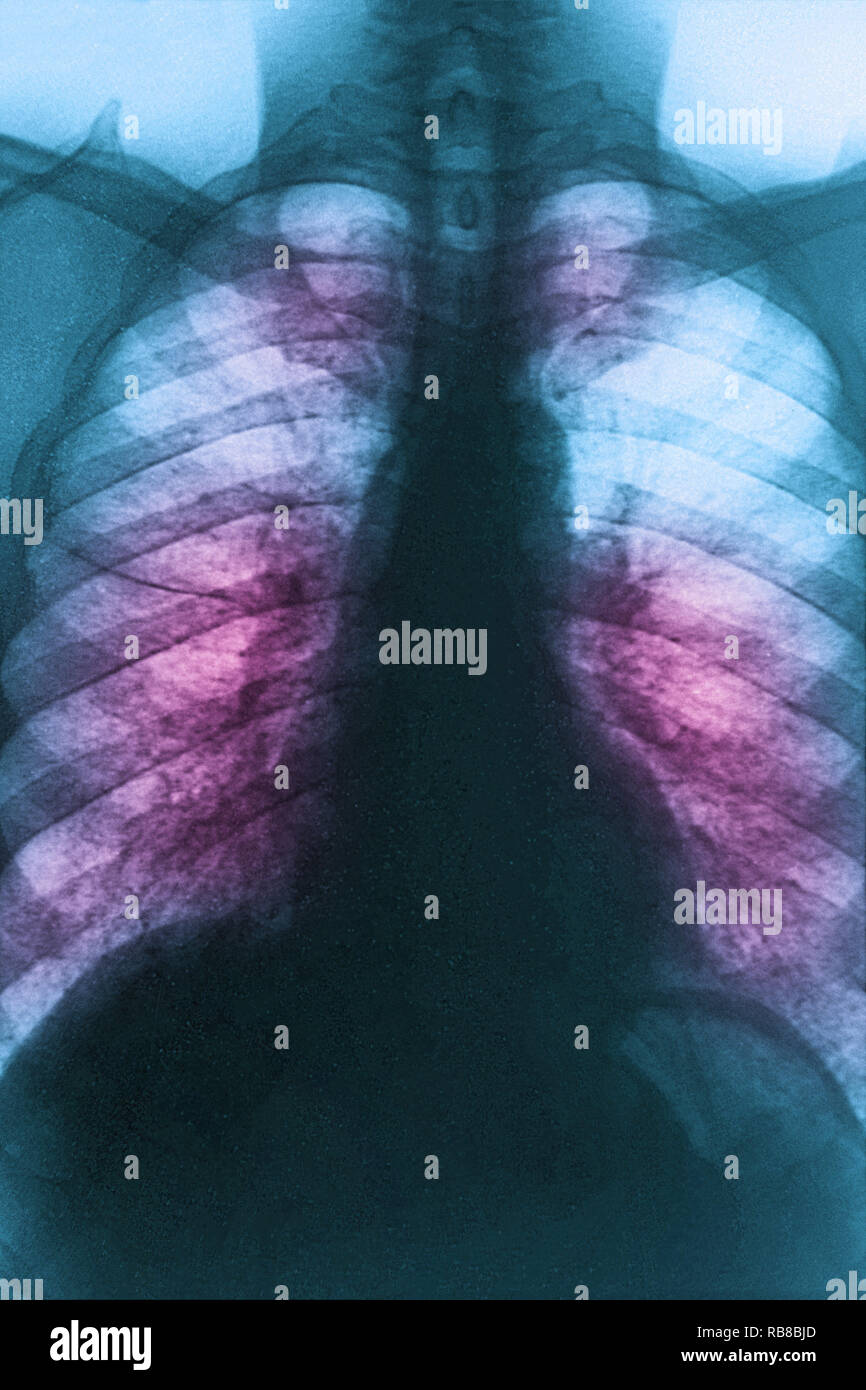

From www.alamy.com

SARCOIDOSIS, XRAY Stock Photo Alamy Sarcoidosis X Ray Images sarcoidosis can involve all of the organ systems of the body, but thoracic lymph nodes and the lung parenchyma are most often and most visibly. this review explores some of the key concepts in the imaging of pulmonary sarcoidosis: abnormalities may be seen on chest radiographs in more than 90% of patients with thoracic sarcoidosis. For patients. Sarcoidosis X Ray Images.